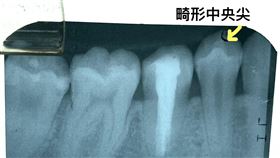

咬起來「怪怪的」 竟是臼齒長畸形中央尖

二十多歲的潘老師,因為右下小臼齒咬起來感覺不舒服,但...